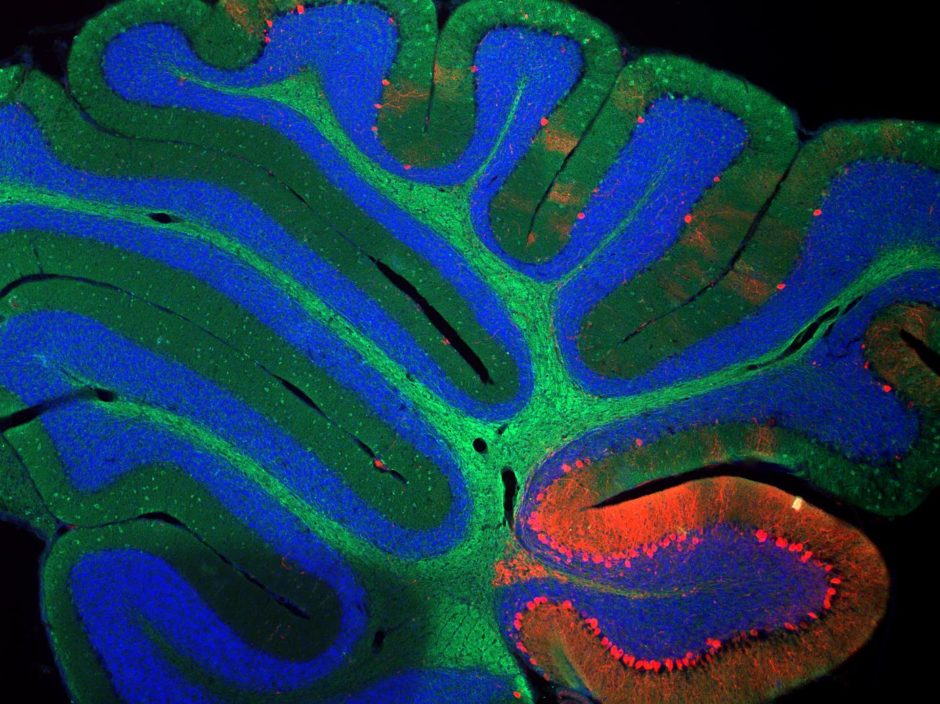

Pattern Recognition: The Math and Science of Mental Reflexes

Your brain is not a computer…or is it? In the last decades, neuroscientists have discovered some pretty amazing things about how living brains process information and help their hosts succeed…